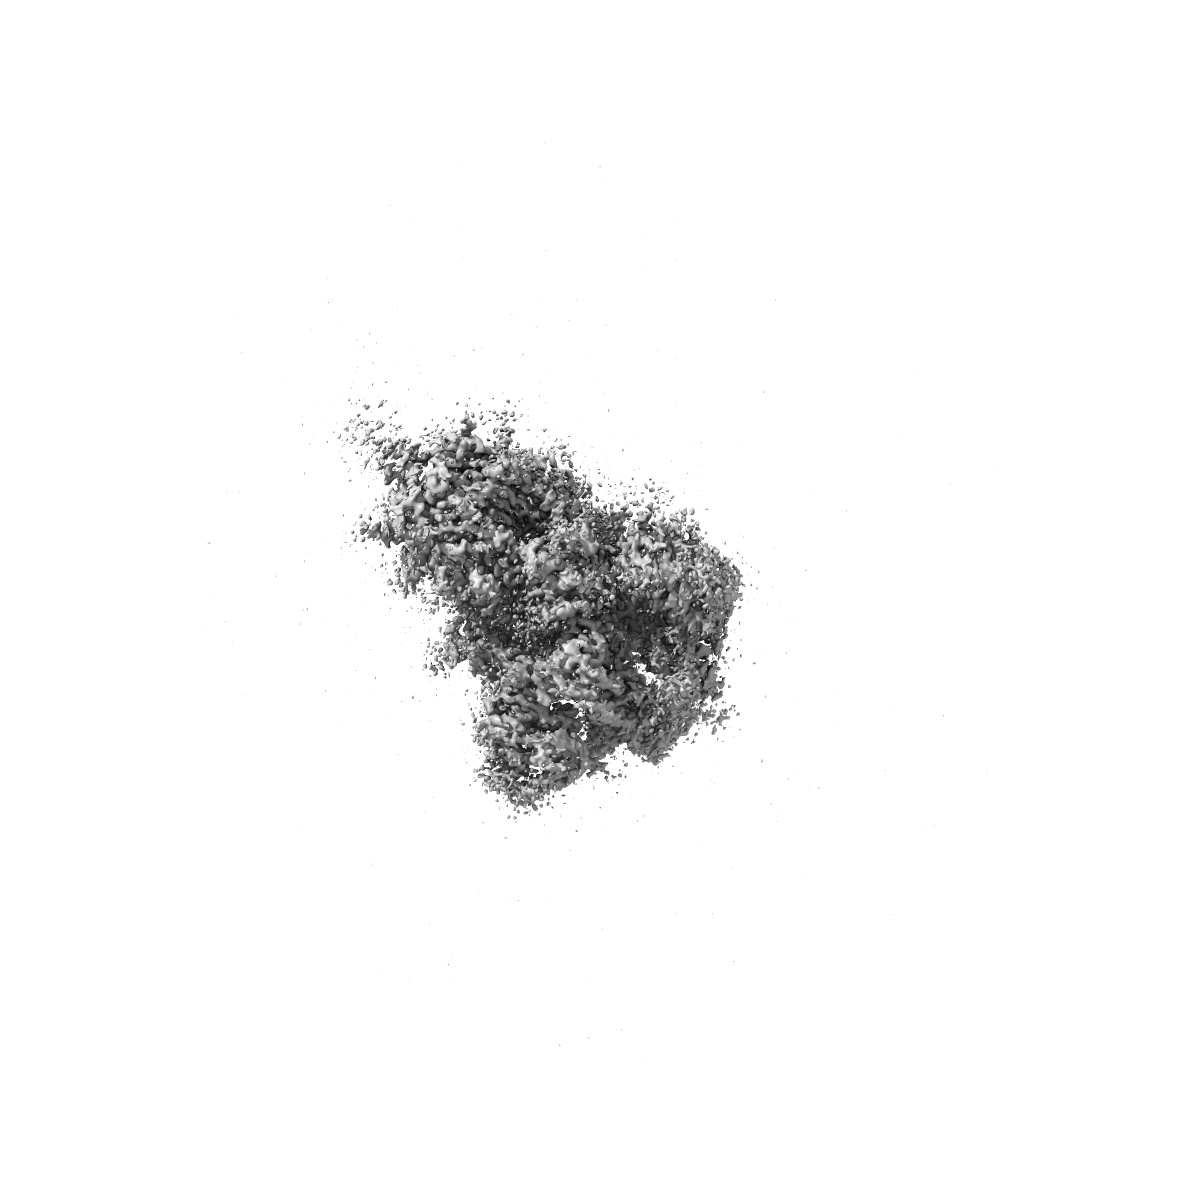

Structure of Covid Spike variant deltaN135 with one erect RBD

Single-particle3.08 Å

Sample: Covid Spike variant deltaN135

Convergence of immune escape strategies highlights plasticity of SARS-CoV-2 spike.

(2023) PLoS Pathog , 19 , e1011308 - e1011308